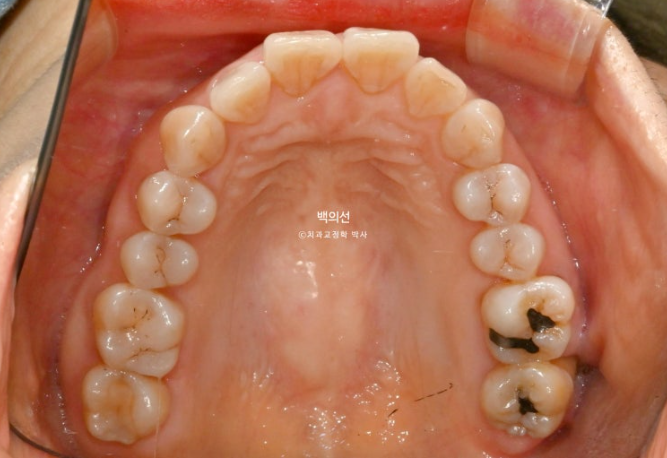

작년 9월, 앞니 돌출과 삐뚠치아 배열을 위해 오신 환자분입니다.

정면에서는 아래 앞니 일부가 윗니에 가려져 안 보일정도의 심한 과개교합을 보입니다.

좌측 아래는 어금니가 빠진 지 오래된 상태입니다.

앞니 두 개가 튀어나와 돌출이며

아래 앞니는 치아가 많이 겹쳐져 있습니다.

특히 가운데 앞니와 옆 앞니는 50% 정도가 겹쳐진 상태